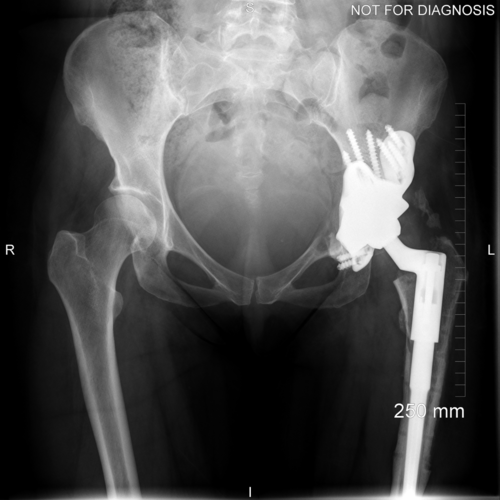

Anteroposterior and lateral plain radiographs demonstrate radiographic features of osteolysis around the acetabular and femoral components. Zara was asymptomatic.

Anteroposterior plain radiograph showing the implant in situ with the surgical clips and a urinary catheter.

Anteroposterior and lateral plain radiographs taken 6-weeks after the operation. Zara was able to bear some weight on her leg with the use of two crutches. Her wound healed well and she was able to raise a straight leg.

Anteroposterior and lateral plain radiographs taken 6-months after the operation. Zara was able to walk without support; she had a good range of movement and was pain free. Her cobalt level was 11.3ppb and chromium level was 21.0ppb – a huge reduction.

Anteroposterior plain radiograph taken at 1-year after the operation. There is no evidence of implant migration. Zara remained pain free and was very happy with the result of her new hip.